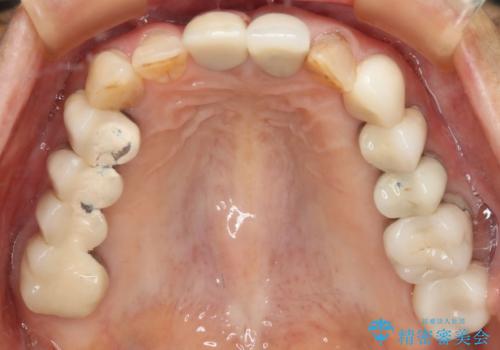

[ 総合歯科診療 ] がたつきの改善とセラミック治療

![[ 総合歯科診療 ] がたつきの改善とセラミック治療の症例 治療前](https://seimitsushinbi.jp/wp/wp-content/uploads/2024/03/f0f438a14c56b185411649f48b5b188c-500x350.jpg?v=1710833163)